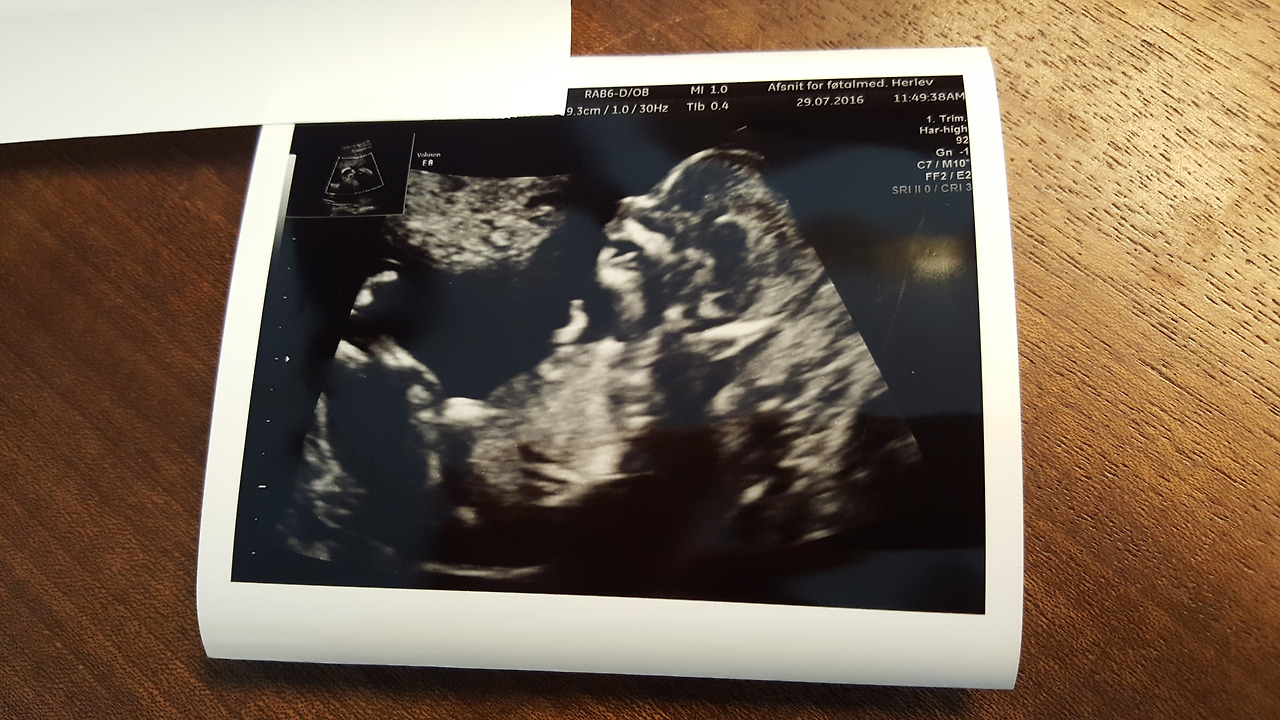

신체검사 등으로 익숙한 차가운 젤의 느낌이 배에 느껴지고 나서 탐촉자가 배에 닿자마자 화면엔 아기의 머리가 바로 나타났습니다. 그냥 신기하고 기쁠 줄만 알았는데, 순간 울컥하더군요. 눈, 코, 입의 위치가 명확히 보였고, 팔, 다리도 그랬으며, 영락 없는 사람의 모양이었습니다. 신체검사로 복부나 갑상선 초음파를 했을 땐, 뭐가 뭔지 모를 종류의 기관들을 의사의 설명만으로 그렇구나 해야 했다면, 이번 초음파로 처음 만난 아기는 완연한 사람의 모습을 하고 있었습니다. 아마 6주에 점으로 표시된 아기를 봤다면 이런 느낌을 받지 못했을 것 같습니다. 이미 10cm에 달하는 아기의 모습을 보며 제 안에 정말 사람이 하나 있구나 싶은 그 강렬한 느낌을 말이지요.

20160729_163452.jpg 저희의 아기입니다. 저희는 태명으로 그냥 한국어로 "아기"라 하고 있어요. 덴마크식으로는 argi라고 쓰고 있지요.

모든 검사가 끝나고 나서는 종합 소견으로 저희 아기가 다운증후군 등 문제가 있을 확률은 지극히 낮은 저위험군에 든다는 이야기를 들었습니다. 얼마나 안도되던지요. 초음파 담당의에게 괜히 엄청 고마움이 느껴졌습니다. 힘든 소식을 전해주지 않은 것에 대해서요.